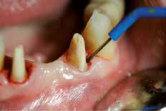

Beispielhaft nun die Anwendug von OXYSAFE am Frontzahn

11. Die Sondierungstiefe beträgt sowohl mesial als auch distal 7 mm an Zahn 11 und es liegt eine Blutung vor. Es liegt ein vertikaler Knochenverlust vor.

Reinigen der Zahnfleischtasche Erste direkte Applikation des Gels in die Zahnfleischtasche Fortsetzung der Behandlung durch den Patienten zuhause 3 täglich 10 ml Zweite Applikation des Gels in die Zahnfleischtasche und dort belassen >> Keine Antibiotika >> Kein CHX >> Über 20 Jahre klinische Erfahrung ca. 2,74 € pro Zahnfleischtasche Aktion Jetzt gratis testen!*